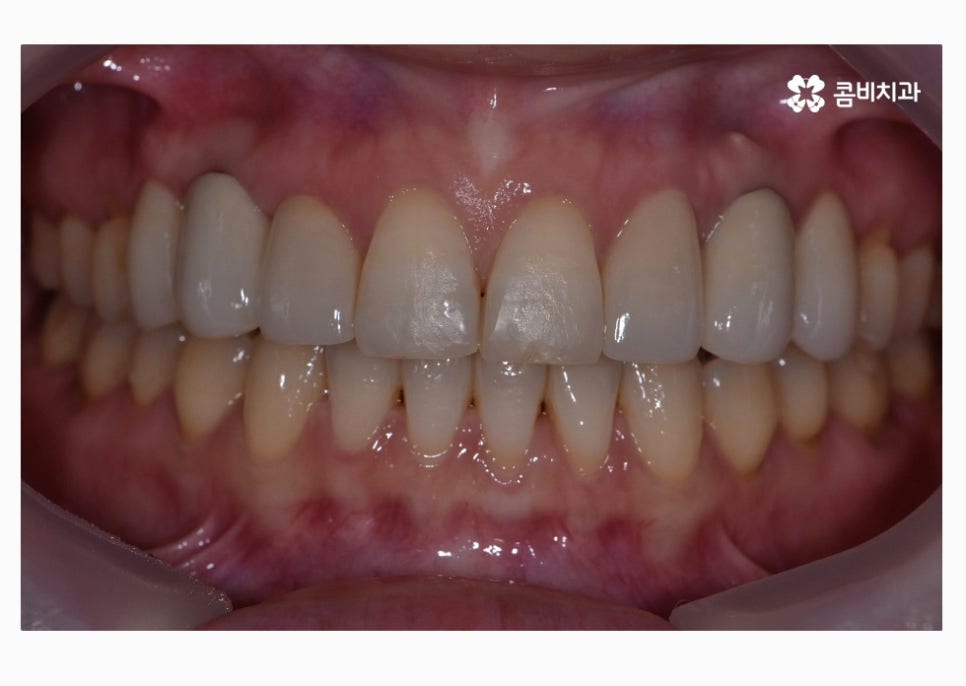

치아교정으로 치열을 가지런하게 하고

30대임플란트 식립까지 잘 마친 상태이며

식립 후에는 골 유착이 튼튼하게 이뤄지는지 기다린 후

주변 치아의 색과 모양에 맞는 보철물을 결합하여

마무리가 된다고 할 수 있어요.

앞니의 경우 심미적으로 중요하기 때문에 임플란트

치료에 있어서 식립 각도부터 보철물의 모양, 색 등

정확해야 하고 연세가 많은 분들의 경우에는